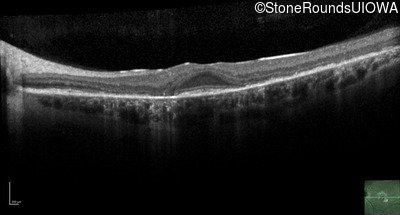

Optical Coherence Tomography - Right - 20/32 +2

Exemplar / OCT Stack